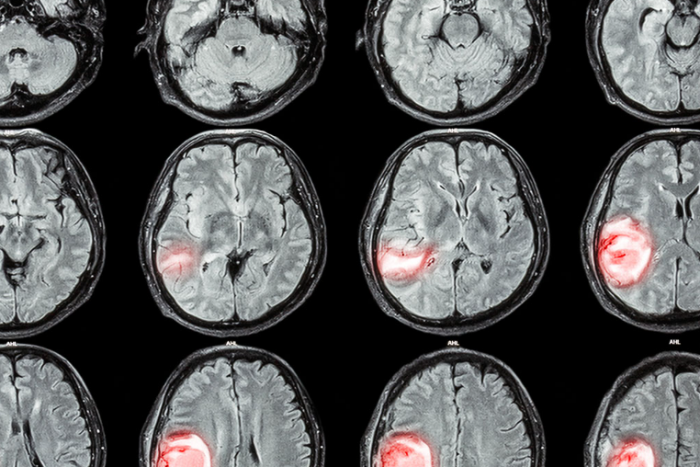

La evolución de las técnicas de diagnóstico molecular ha permitido detectar nuevas alteraciones genómicas, que son susceptibles de provocar un fenotipo tumoral, así como tener más precisión en la detección de las ya conocidas. En este programa, TECH te presenta los principales tratamientos agnósticos dirigidos a diferentes patologías, con el fin de que el alumno amplíe sus conocimientos y sea más preciso en su profesión, especializándose en un área específica que continuamente demanda profesionales, dada la singularidad de la patología. Con todo, el plan de estudios propuestos es único, cuyo temario de calidad guiará al profesional hacia la excelencia del sector.

1.9. Hacia el tratamiento agnóstico en tumores del SNC